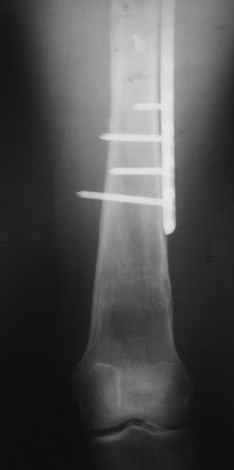

Re: Перелом проксимального отдела диспластичного б

Прошу прощения, со снимками глюк произошел. Высылаю. С уважением Евгений У.